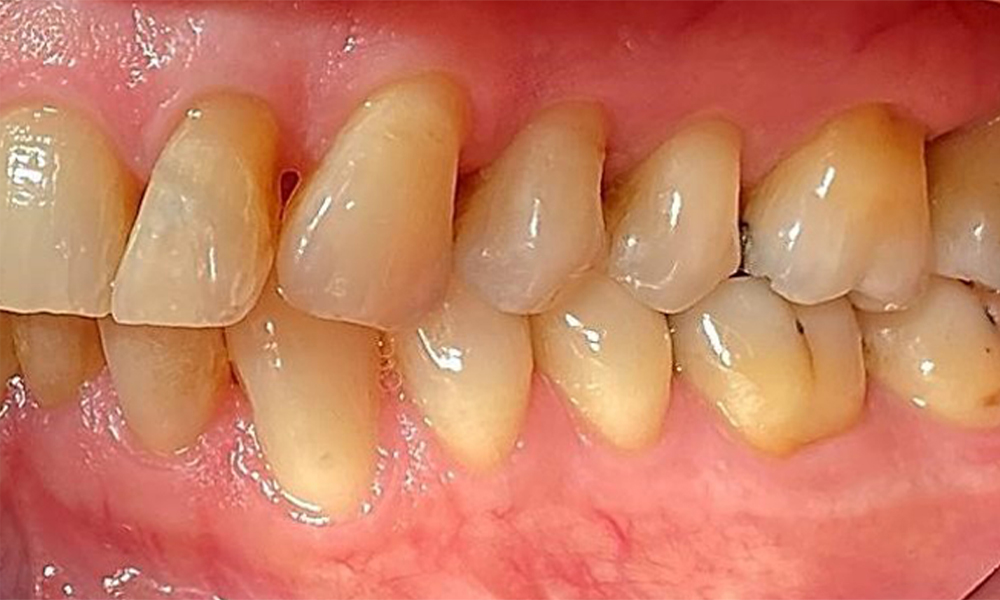

Right lateral view. Loss of the interdental papillae.

Fig. 3 Right lateral view. Loss of the interdental papillae. © Dr R. Krapf

The patient has stage II, grade B periodontitis (5). At 1 to 3 mm, the clinical probing depths were within the physiological range. Localized probing depths of 5 mm were observed on the mesiopalatal aspects on both 17 and 27. There are generalized recessions of 1–3 mm with partial loss of the interdental papillae (Fig. 2, Fig. 3, Fig. 4)